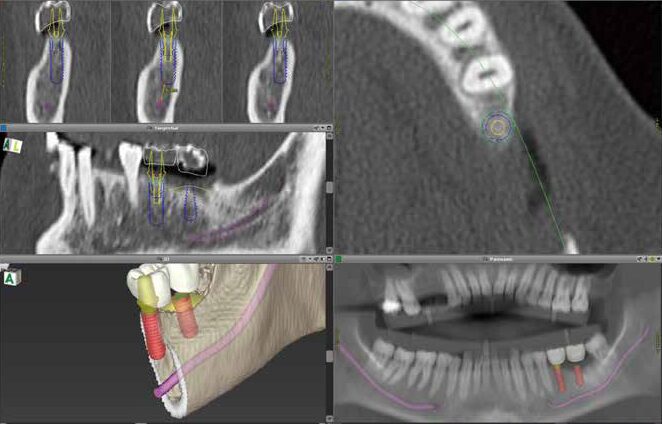

ガイド

インプラント手術に

患者さまの

あらゆる

患者さまに